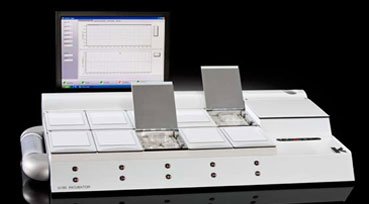

In Vitro Fertilization (IVF) is a process in which the egg is fertilized by sperm outside mother’s womb in strictly controlled laboratory environment which simulates mother’s womb. This process is done in special incubators and embryos are kept there till they are ready to be transferred to mother’s womb.The entire process includes monitoring the women’s ovulation cycle and regulating it by hormones if necessary, picking up the ovum from mother’s ovary under doppler guidance in special IVF operation theater and setting sperm to fertilize it in the adjoining hi tech IVF laboratory, the fertilized egg now called “zygote” is transferred into the uterus. Kilkari Fertility Centre is proud to announce that it is equipped with two of the world’s best incubators so that your embryos get nothing but the best to maximize the chances of pregnancy. Having more than one incubator also helps against even the slimmest chance of machine failure. In Vitro Fertilization (IVF) is a process in which the egg is fertilized by sperm outside mother’s womb in strictly controlled laboratory environment which simulates mother’s womb. This process is done in special incubators and embryos are kept there till they are ready to be transferred to mother’s womb.The entire process includes monitoring the women’s ovulation cycle and regulating it by hormones if necessary, picking up the ovum from mother’s ovary under doppler guidance in special IVF operation theater and setting sperm to fertilize it in the adjoining hi tech IVF laboratory, the fertilized egg now called “zygote” is transferred into the uterus. Kilkari Fertility Centre is proud to announce that it is equipped with two of the world’s best incubators so that your embryos get nothing but the best to maximize the chances of pregnancy. Having more than one incubator also helps against even the slimmest chance of machine failure. |